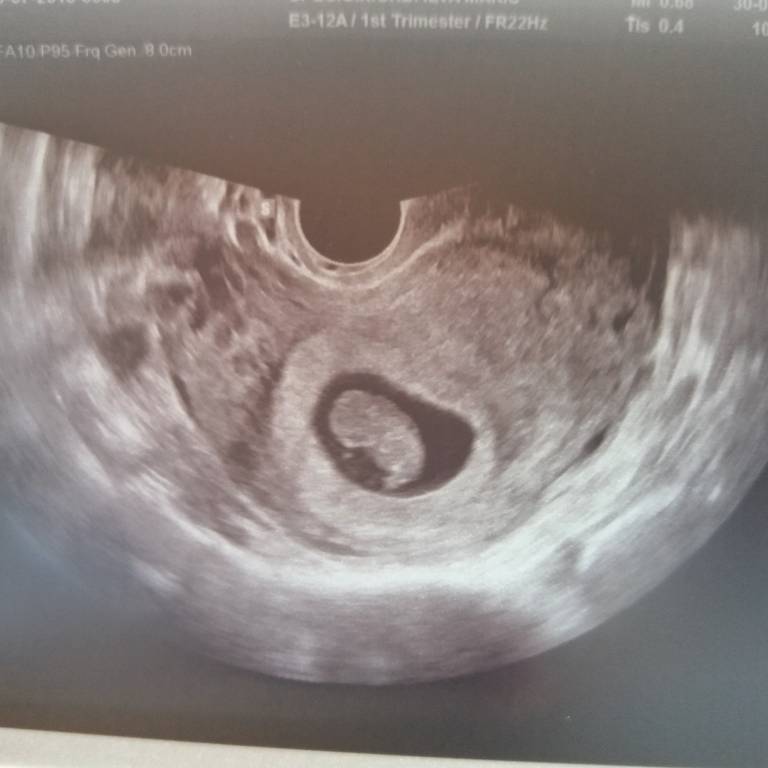

Ogolnie u mnie wszystko ok, wczoraj 8t6d mialam USG i maluszek ma juz 2,2cm i serce wali 170 na min

Niestety zeby wszystko nie bylo tak idealnie mam krwiaczka

Zobacz załącznik 883178